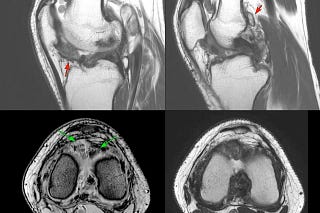

COD 134 - Epiphyseal Involvement and The Skip Lesion

15-yrs old diagnosed with osteosarcoma of the distal left femur.